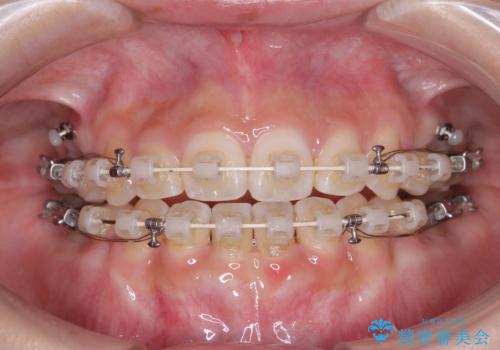

- 矯正装置

- 審美装置

舌のトレーニングをしっかりと行ってくださり、1年半という非常に短い期間で仕上げることができました。